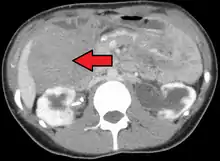

Desmoid tumor as seen on CT scan